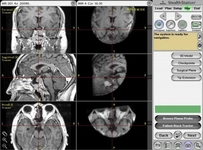

Hipofiz Bezi Tümörlerinin TeşhisiHipofiz bezi tümörlerinin teşhisi genellikle aşağıdaki yöntemlerle yapılır: